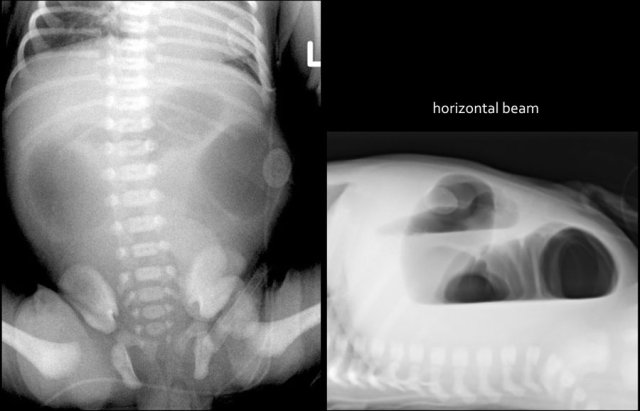

Radiographs will show multiple dilated bowel loops and absence of air in the colon as seen on the image on the left.

A colon enema will show a microcolon with contrast filling ending blind in the ileum (arrow on image on the right).